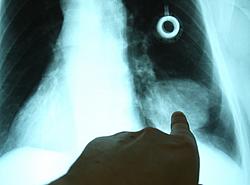

Bronchialkarzinom

In Zusammenarbeit mit dem Pulmonologen (Lungenfacharzt) erfolgt zunächst eine umfangreiche Diagnostik. Hierzu zählen u.a. die Computertomographie, die Bronchoskopie (Lungenspiegelung) und Lungenfunktionstests. Je nach Tumor oder Patient kommen noch Szintigraphien oder ein Belastungs-EKG in Frage.

Nach Bestimmung der feingeweblichen Art, Größe, Lage, Ausdehnung und Lymphknotenbefall wird die Operation angestrebt mit dem Ziel den Tumor komplett zu entfernen.